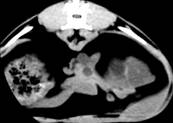

Рис.6. Серія КТ

сканів нирок кота. Кисти нирок, більше зліва

Даний факт знаходить підтримку у роботах

сучасних дослідників гуманної медицини в цій галузі. Досліджуючи цю тварину

через 14 днів, ми відзначили зниження інтенсивності сигналу вищевказаного

кістозного утворення (рис.).

Поясненням цього може бути поступовий розпад гемоглобіну, що зменшує

інтенсивність сигналу. Це припущення також висувається у гуманній медицині. В

той же час, інтенсивність деяких кістозних утворень залишалась постійно

високою, що може вказувати на інфікування вмісту кісти та зумовлене наявністю

великої кількості білка у кістозній рідині. Така тенденція знаходить

відображення у деяких публікаціях.

Рис.7. КТ

нирок кота. Полікистоз в стадії компенсації: а-неускладнена кіста; б -

геморагічна кіста

Рис. 8. КТ

кота. Полікистоз нирок у стадії субкомпенсації. Деформація

миски

правої

нирки.

Зменшення

інтенсивності

сигналу

геморагічної

кісти

(а)